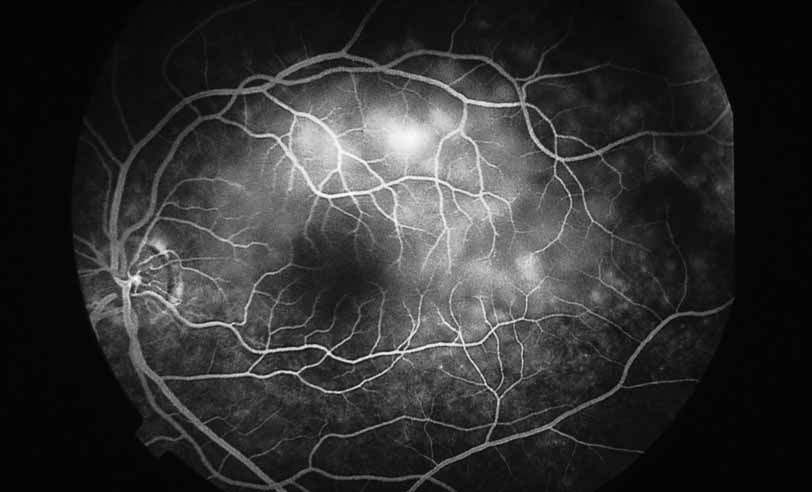

A third instance in which fluorescein angiography concentrating on the optic nerve may be helpful is in eyes with vascular engorgement of the optic nerve, especially with media opacities. Fluorescein angiography may help the clinician distinguish abnormally leaking capillaries from neovascularization. In acute multifocal hemorrhagic retinal vasculitis, optic nerve involvement is common in the early stages of the disease, 47 with optic nerve disc neovascularization seen later (see Figs. 10, 11, 12, and 13). Another fluorescein angiographic clue to the distinction between optic disc vessel engorgement and true neovascularization is the presence of associated large zones of retinal capillary nonperfusion such as those seen in sarcoidosis (see Figs. 14 and 15),34–40 acute multifocal hemorrhagic retinal vasculitis (see Figs. 10 and 11),47 or Eale disease (see Figs. 16 and 17).48–52

Fig. 12 Acute multifocal hemorrhagic retinal vasculitis. The patient later developed disk neovascularization with vitreous hemorrhage. Note the areas of neovascular leakage from the optic nerve.

Fig. 13 Acute multifocal hemorrhagic retinal vasculitis. The patient underwent scatter laser photocoagulation to the zones of retinal capillary nonperfusion, which resulted in regression of the neovascularization.